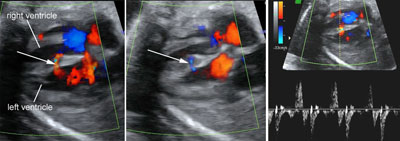

Color and pulsed Doppler of blood shunting across a muscular ventricular septal defect

Legend:Color and pulsed Doppler of blood shunting across a muscular ventricular septal defect

Muscular ventricular septal defect

Legend:Muscular ventricular septal defect